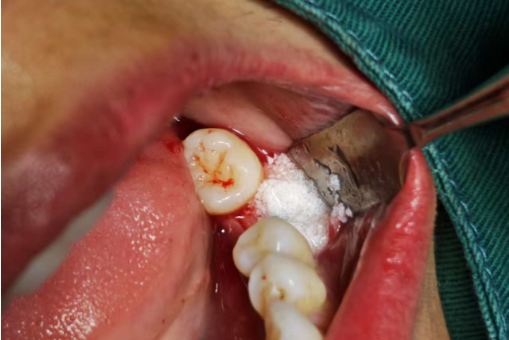

One of the primary drawbacks of neglecting missing teeth is the significant escalation in implant treatment costs. When a tooth is extracted, the alveolar bone immediately begins a process of resorption—biological breakdown triggered by the loss of mechanical stimulation from the tooth root. Immediate or early implant placement (within 3–4 months post-extraction) often allows for straightforward implantation without bone grafting, as the alveolar ridge maintains its structural integrity. However, prolonged edentulism (tooth absence) leads to progressive bone loss. By the time implantation is delayed beyond 6 months, most patients require bone grafting procedures (e.g., autogenous, allogeneic, or alloplastic grafts) to restore sufficient alveolar volume. Additionally, a resorbable membrane (e.g., collagen membrane) is frequently used to enhance graft stability and prevent soft tissue infiltration, adding further to material and procedural costs. These supplemental steps can increase treatment expenses by 30–50% compared to timely implant placement.